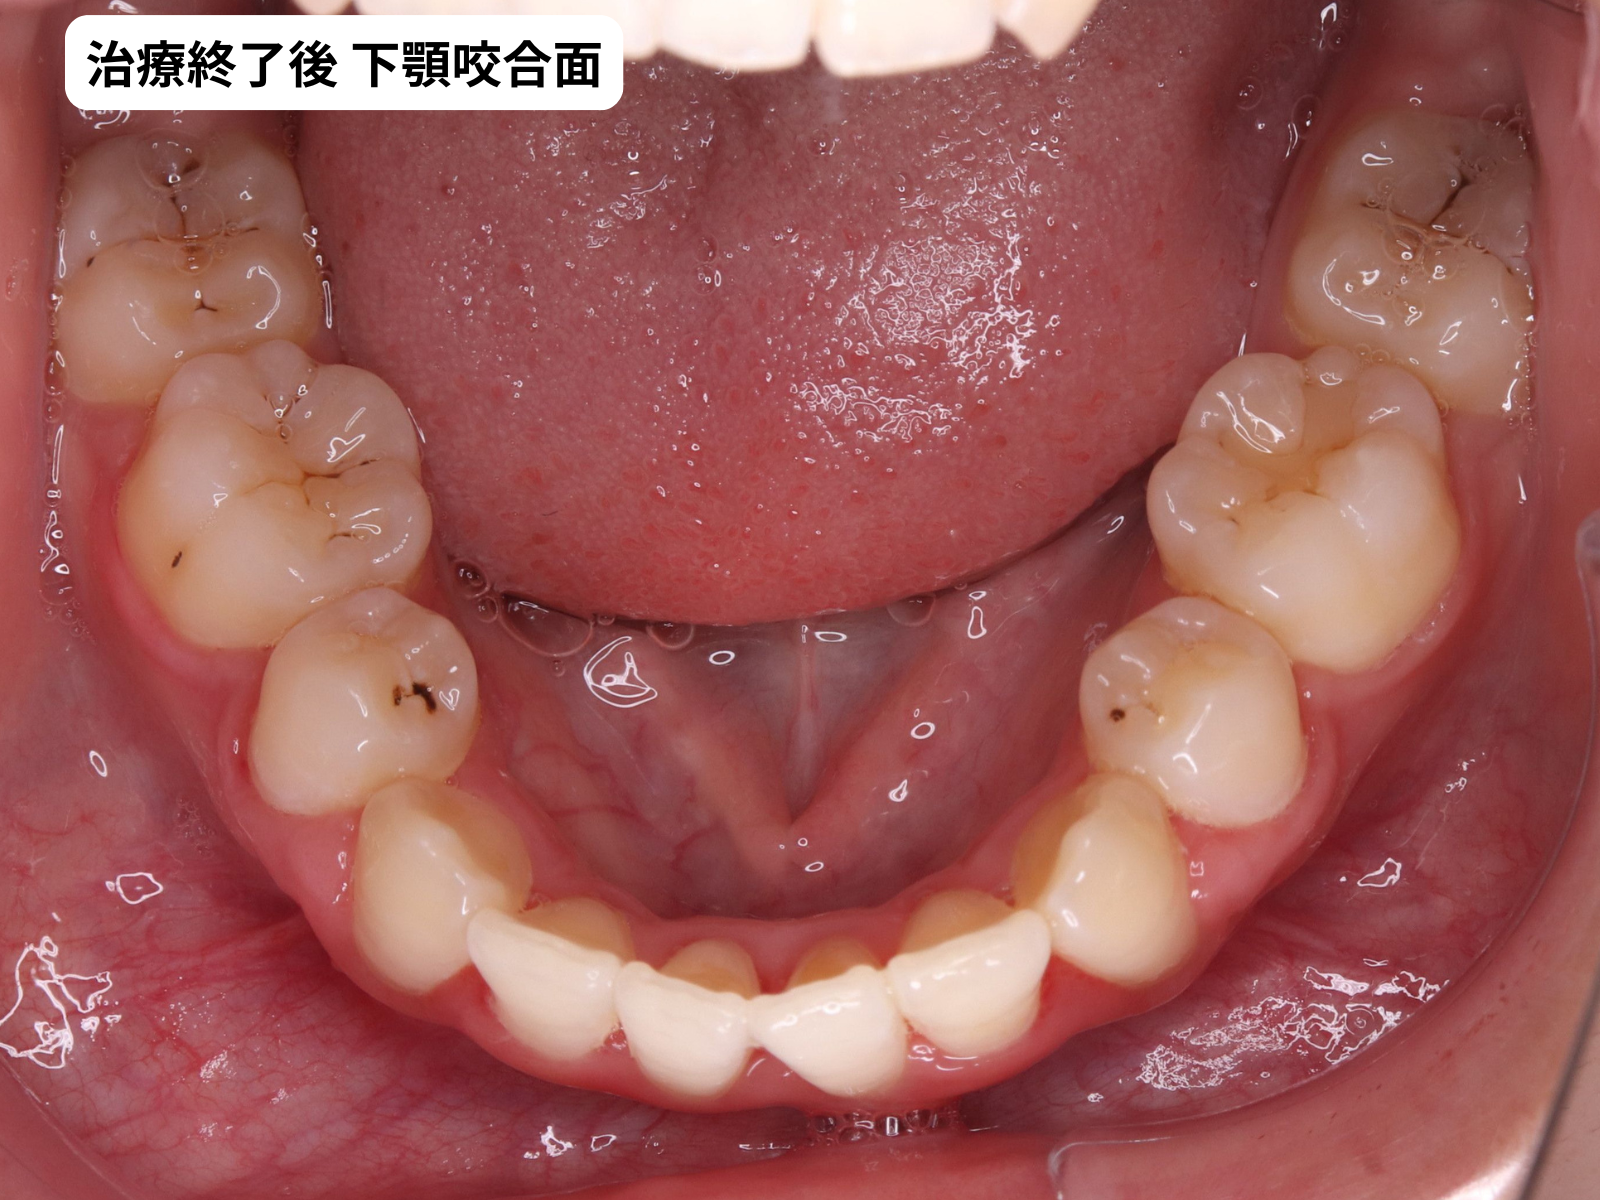

治療終了後の口腔内

(初診時のBeforeは上の5枚法をご参照ください)